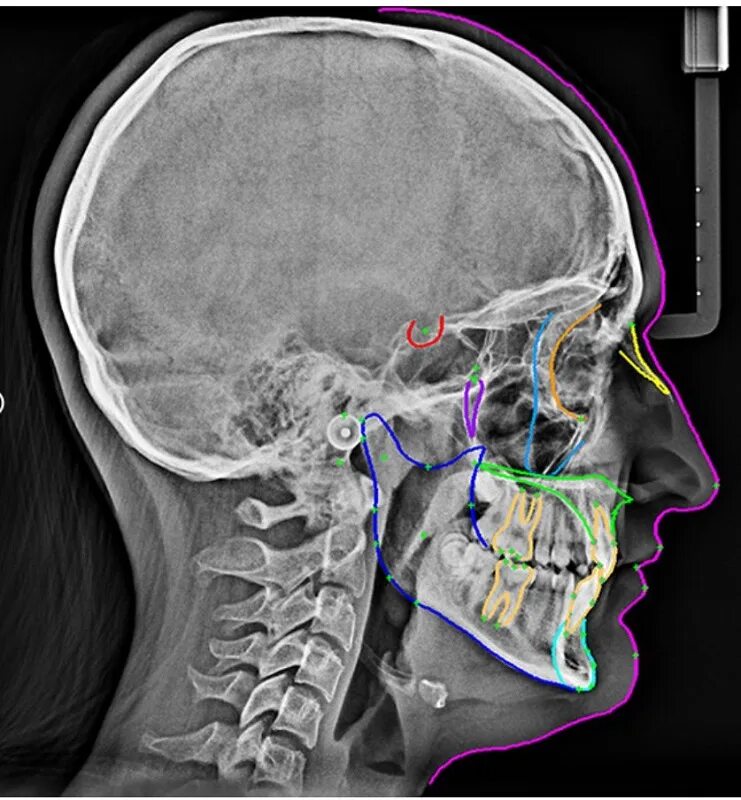

Трг проекции